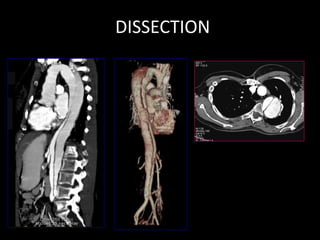

• Dissection flap at the root of aortaNormal

• ANEURYSM

• CT- Large saccular ascending aortic aneurysm 7cm

diam,2.5cm eccentric thrombus, L=10.5 cm. origin of

brachiocephalic, carotid, subclavian Artery from sac and e/o

narrowing of ostium. Mild compression of main and left

pulmonary artery. Mild pericardial effusion.

DISSECTION